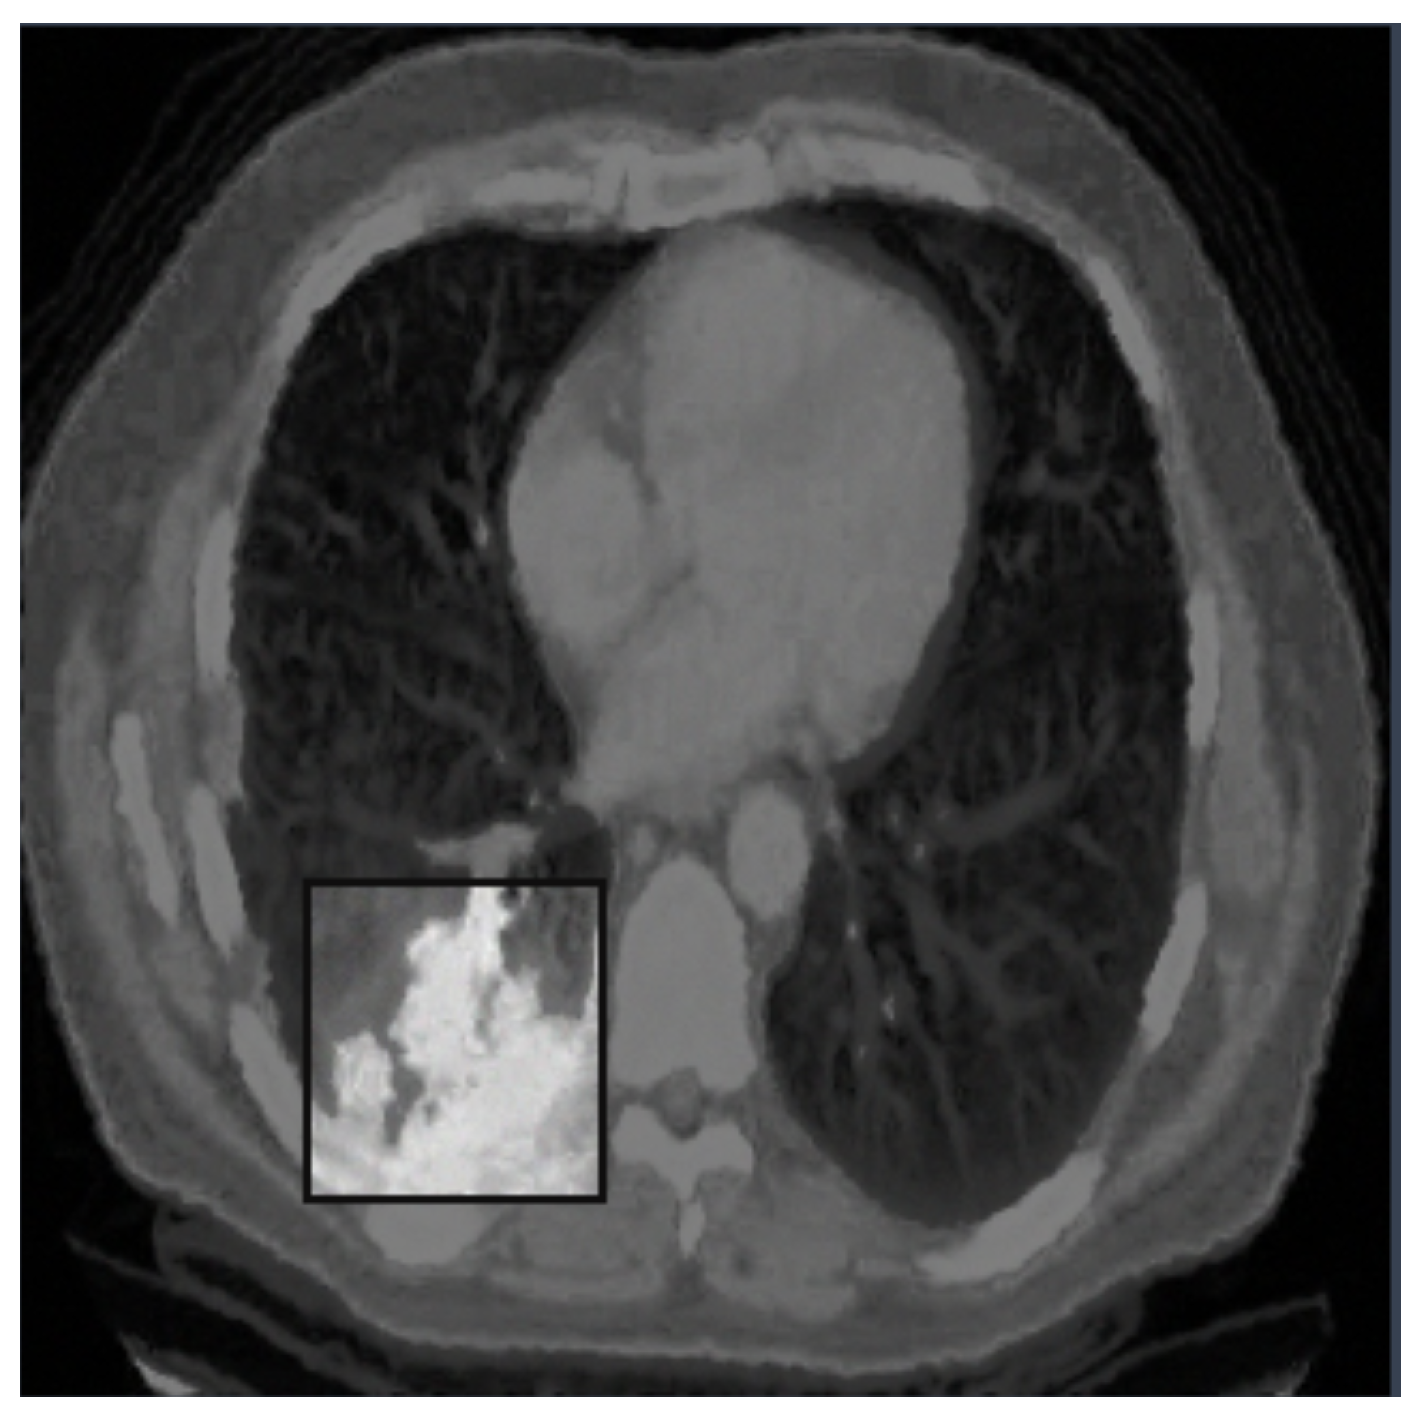

- Adenocarcinoma (Blue Line):

- -

- The blue line represents the precision–recall relationship for the adenocarcinoma class.

- With an average precision (AP) of 0.734, the model performs relatively well in detecting adenocarcinoma, maintaining high precision and recall values.

- Cancer (Orange Line):

- The orange line represents the performance for the cancer class.

- An AP of 0.588 indicates moderate performance, with a noticeable drop in precision as recall increases, suggesting that the model struggles more with this class compared to adenocarcinoma and nodules.

- Nodule (Green Line):

- The green line shows the precision–recall for nodules.

- With the highest AP of 0.802, the model performs best on this class, indicating high precision and recall across most thresholds.

- All Classes (Bold Blue Line):

- The bold blue line represents the overall performance across all classes, with an mAP@0.5 of 0.708.

- The mean average precision (mAP) at an IoU threshold of 0.5 provides a single metric summarizing the model’s performance across all classes.

- An mAP@0.5 of 0.708 suggests that the model has a strong overall detection capability, balancing precision and recall well.